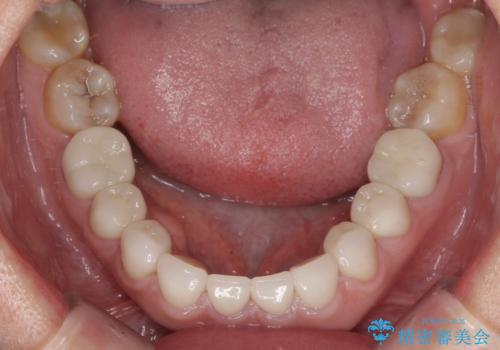

上顎前歯は樹脂を外し、下顎前歯の隙間はそれぞれの歯を大きくするように補綴治療を行うことで隙間を埋めることとしました。

口を開けたときに見える範囲をオールセラミッククラウンとし、とても自然な口元に仕上げることができました。